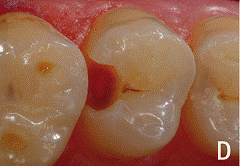

При этой форме кариозного процесса целостность

эмалево-дентинного соединения нарушается при этом зондирование границы

болезненно, однако под полостью зуба сохраняется достаточно толстый слой

дентина. При осмотре зуба обнаруживается неглубокая кариозная полость,

заполненная размягчённым, пигментированным дентином, что определяется при

зондировании.

При наличии размягчённого дентина в фиссуре зонд

задерживается, застревает в ней. При хроническом течении кариеса при

зондировании выявляется плотное дно и стенки полости, широкое входное отверстие.

При остротекущей форме кариеса - обилие размягчённого дентина на стенках и дне

полости, подрытые, острые и хрупкие края. Пульпа зуба реагирует на силу тока

2-6мкА.